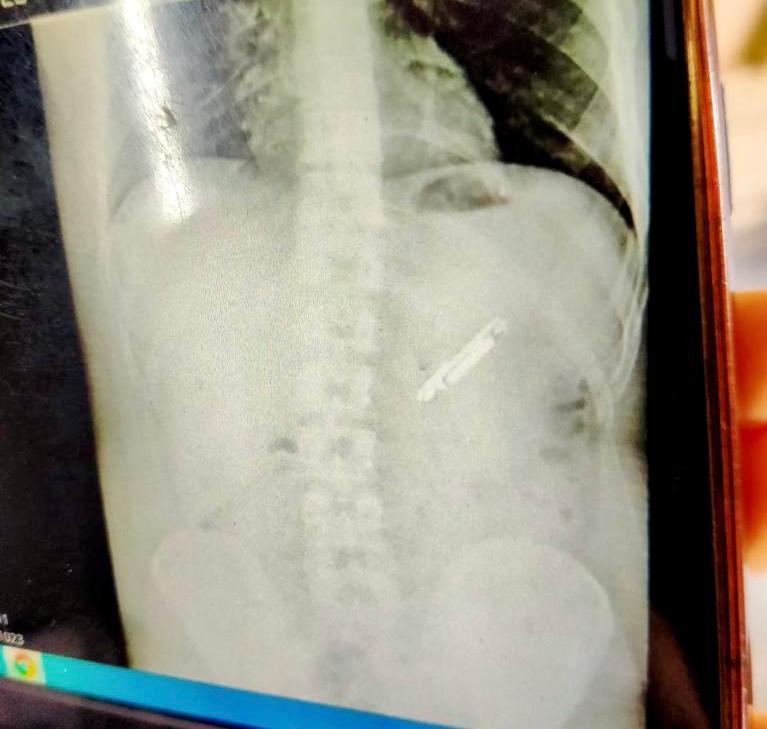

نجح فريق طبي بمستشفى الطوارئ الجامعي بطنطا، في إنقاذ حياة مريض ابتلع عن طريق الخطأ هاتف محمول حيث تم استخراج المحمول عن طريق بالمنظار وبدون أي تدخل جراحي.

أوضح الدكتور أحمد غنيم عميد كلية الطب بجامعة طنطا أن مستشفى الطوارئ الجامعي استقبل شابًا، في حالة حرجة جدًا بعد ابتلاعه لهاتف محمول عن طريق الخطأ منذ أكثر من شهرين، واستقر في المعدة وبداية الاثني عشر، مما شكل تهديدا كبيرا على حياته بسبب حالة من القيء المستمر والانتفاخ بالبطن مع تيبس كامل في عضلات البطن مع احتمالات حدوث النزيف الداخلي او الانسداد المعدي او المعوي، مما استدعى التدخل السريع من الفريق الطبي المتواجد بالمستشفى الجامعي بأجراء منظار علاجي بدون أي تدخل جراحي، ونجح الفريق الطبي في انقاذ حياة المريض واستخراج الهاتف المحمول، مشيرا أن عملية استخراج الهاتف المحمول استغرقت ساعة كاملة.